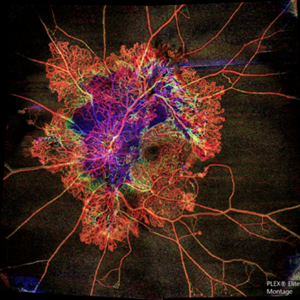

Flame of the Forest

Apr 9 2020 by Daraius N Shroff, MS FMRF FRCS

A 54-year-old man with DM for 15 years. The left eye had a visual acuity of 20/40. Wide field swept source OCTA revealed branching out central neovascular trunk vessels from the disc with terminal loops, along with exuberant proliferation of irregular small-calibre fine new vessels. The patient underwent OCTA guided pan retinal photocoagulation.

Photographer: Anuj Choudhary, Shroff Eye Centre, New Delhi

Imaging device: Zeiss Plex Elite 9000

Condition/keywords: proliferative diabetic retinopathy (PDR)